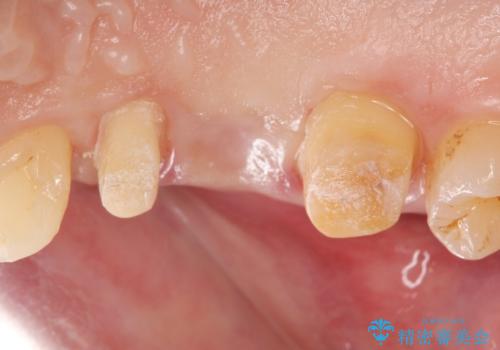

また噛み合わせが深くブリッジの強度が十分に確保できないことから、抜歯時に歯周外科を行うことで十分に安定したクラウン装着をできるような処置を行っています。

術前・術後でブリッジ治療をした部分の歯肉ラインを整えたことで安定したブリッジを製作することができました。